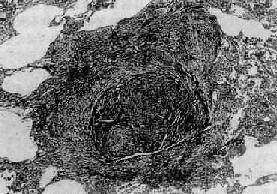

图9-22 矽肺

矽结节,由呈旋涡状排列的已发生玻璃样变的胶原纤维构成